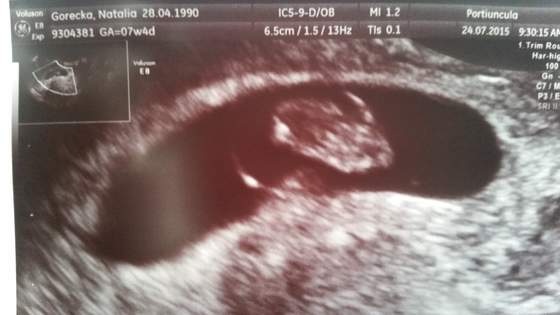

Przedstawiam oto Junior) Wg usg 7 tydzien 1 dzien

Serducho bije

11mm slodyczy

Zobacz załącznik 702272